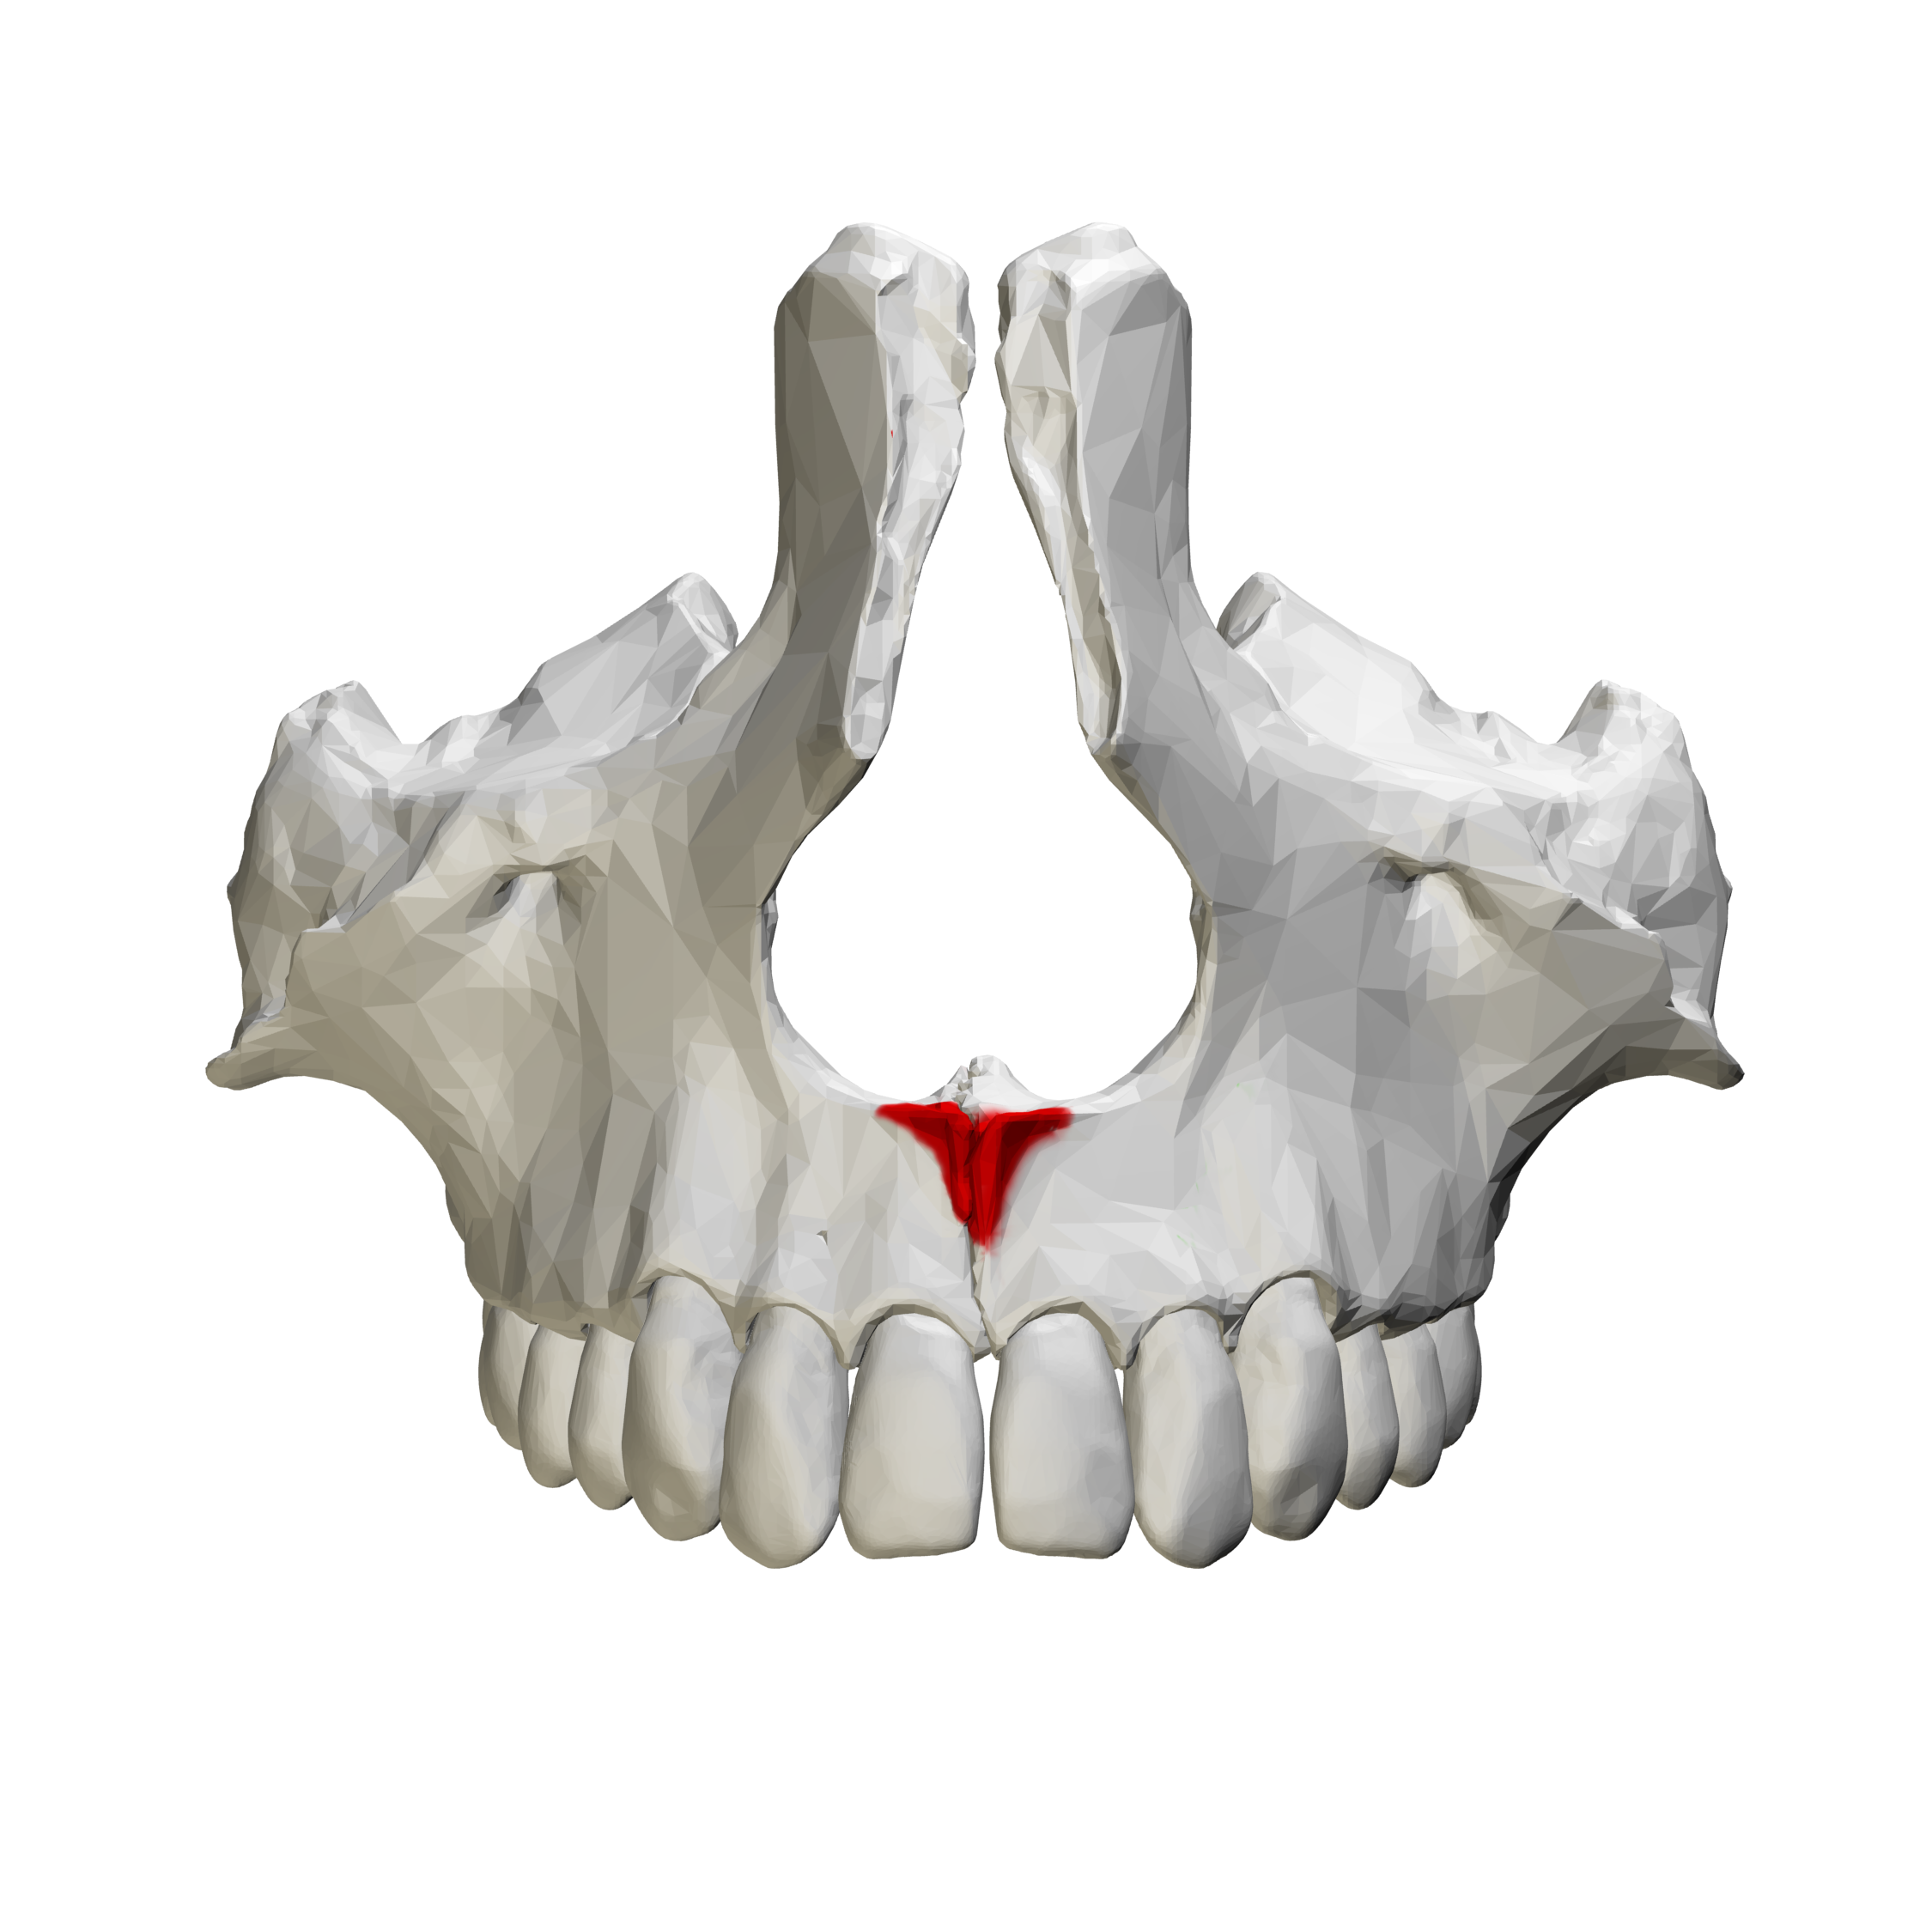

anterior nasal spine

sharp projection of maxilla located at anterior inferior portion of nasal cavity and septum

v shaped radiopaque area located at the intersection of floor nasal cav and septum, may be seen